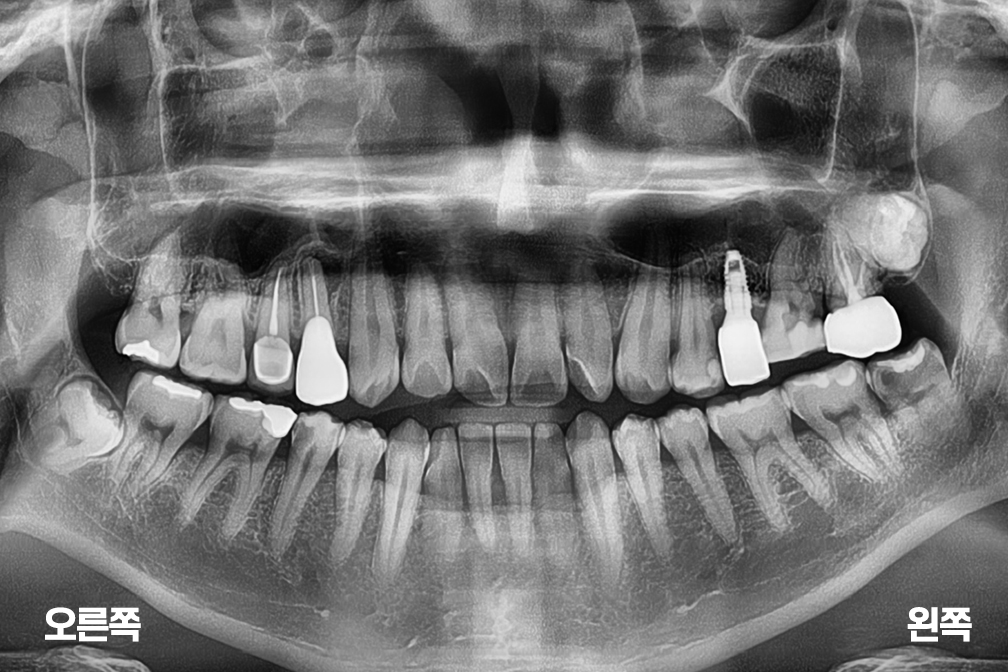

임플란트 수술

After 2026년 3월 6일